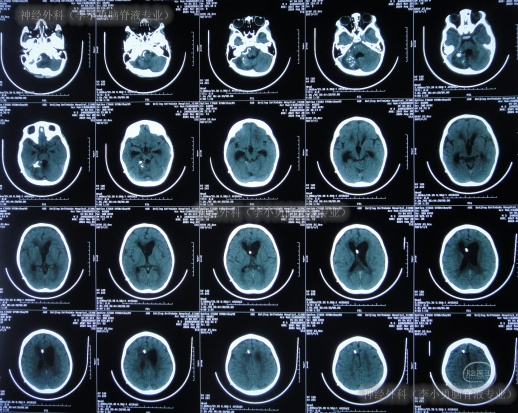

入院后17天即2024年6月19日,变得能经口进食拔除鼻饲管(图-12);查头颅CT示引流术后状态(图-13)。

图-12:2024年6月19日

图-13:2024年6月19日头颅CT